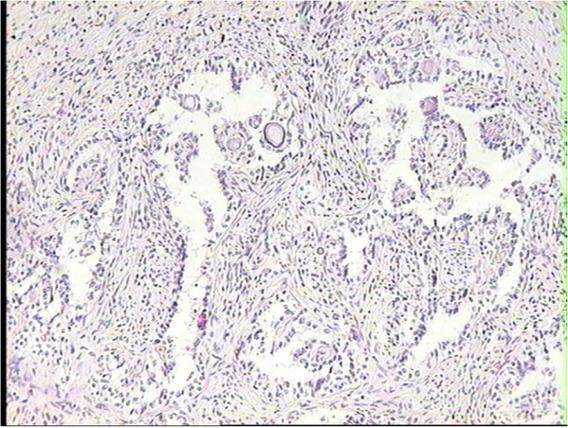

The tumour cell structure had characteristic focal blood vessel proliferation. In the periphery of the blood vessels, the walls were cuffed with neoplastic epithelioid cells (Fig. 4). In less advanced tumour tissue growth, the proliferation was mainly localised in the ovarian hilus. In cases with more advanced tumour proliferation, PEComa tissue reached the ovarian cortex border, but never grew beyond the ovarian capsule (Figs 5 and 6). There was some relation observed between the stages of the tumour tissue proliferation and the structure of PEComa neoplastic cells. In advanced tumour tissue growth, the neoplastic cells were smaller, with condensed hyperchromatic nuclei (Fig. 7), which may indicate the progress in their anaplastic changes.

Anaplasia of cells seen in the PEComa tissue infiltrating the gonadal stroma in the ovary of a dairy cow with an adenomyotic uterus. HE, 20×